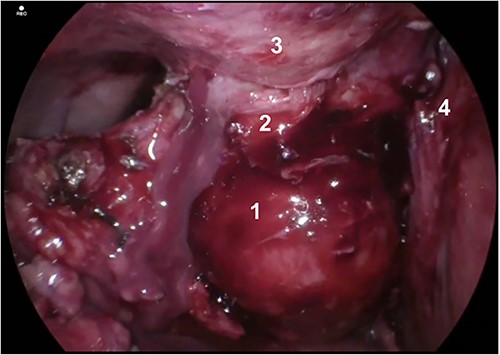

Post-drain removal, the patient was booked for elective laparoscopic cholecystectomy. An infraumbilical port was inserted to achieve pneumoperitoneum, and further ports were inserted based on ergonomics (Fig. 3). Initial adhesiolysis and dissection of the gallbladder from the greater omentum and anterior abdominal wall proved challenging. After freeing the fundus, the gallbladder was found to be full of pigmented stones, many of which had migrated into the fistula tract (Fig. 4). The fistula tract was opened from the intra-abdominal aspect and all gallstones were laparoscopically retrieved, with some stones found to have migrated as far as the umbilical port in the midline (Fig. 5). A subtotal cholecystectomy was performed, leaving a small part of the Hartmann’s pouch in situ as it was unsafe to dissect lower. The pouch was closed with absorbable sutures. Drains were placed in the subhepatic space and pelvis.

Internal opening of fistula tract after dissection of the gallbladder fundus away from the anterior abdominal wall. A gallstone is shown lodged in the fistula tract with further gallstones embedded more superficially.